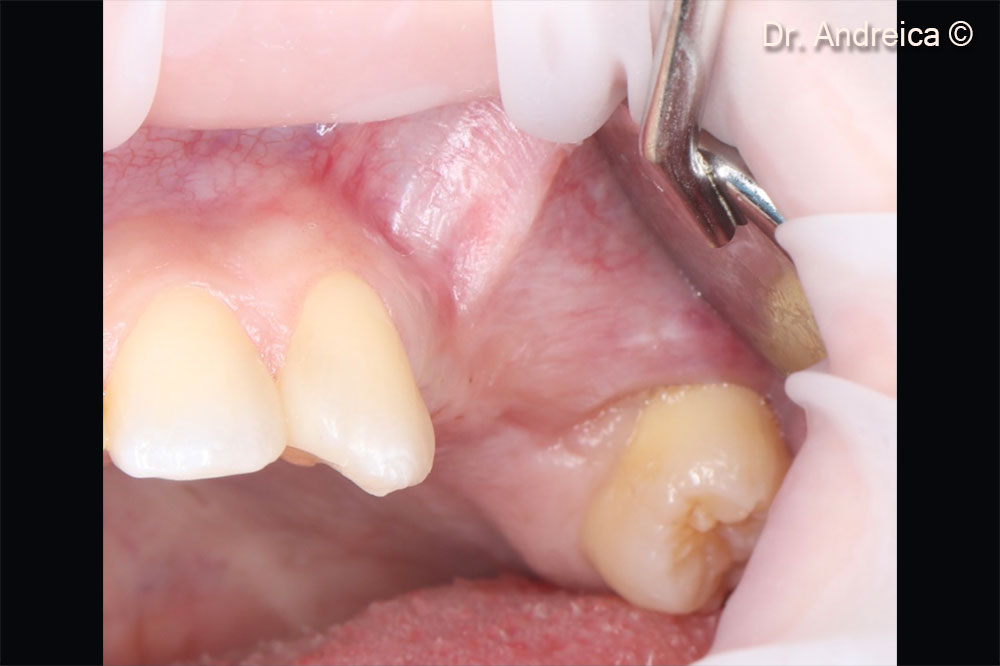

Buccal view of the posterior left maxilla showing a lack of the vestibule and a mucogingival line displaced palatally